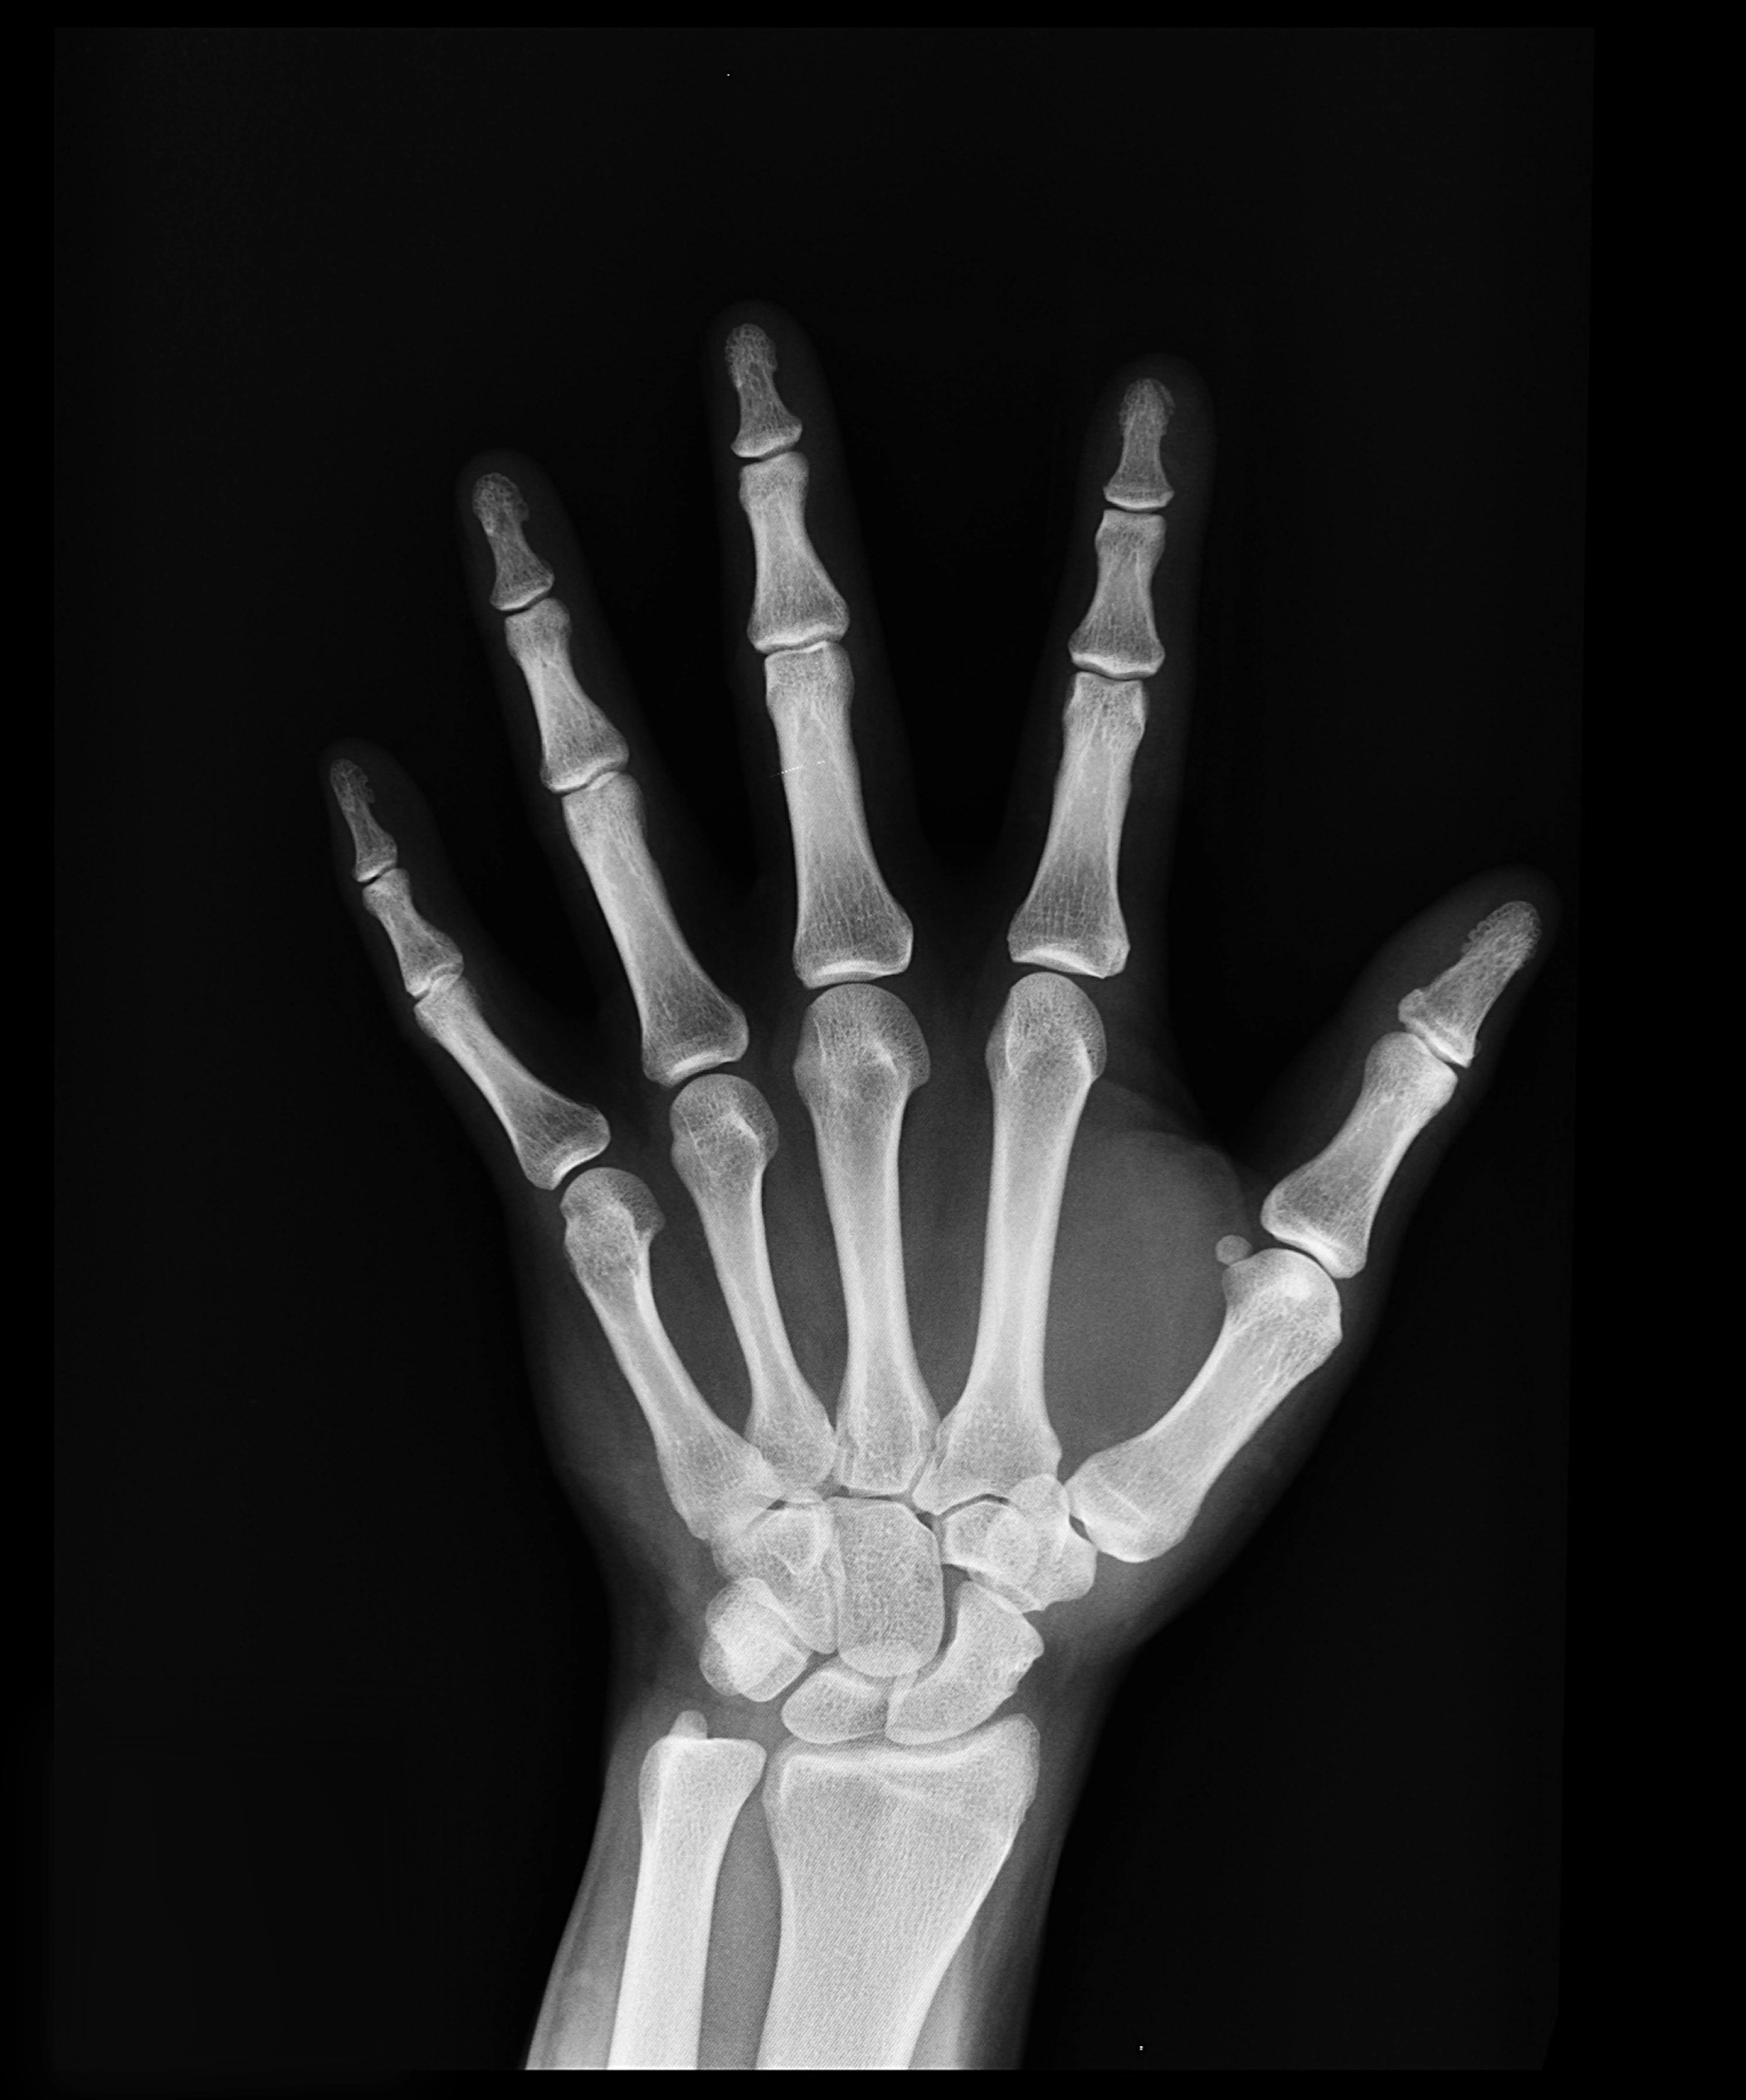

콘드로이친(Chondroitin)은 우리 몸의 연골과 결합조직 속에 자연적으로 존재하는 성분으로

관절 사이에서 충격을 흡수하고 마찰을 줄여주는 역할을 합니다.

나이가 들면서 콘드로이친이 점점 감소하면 관절이 뻣뻣해지고 통증이 생길 수 있다고 합니다.

콘드로이친 효능 2 – 연골 보호 및 재생 도움

콘드로이친은 단순히 통증을 완화하는 것에 그치지 않고,

-연골 세포의 손상을 줄이고 재생을 돕는 역할도 합니다.-

콘드로이친 효능 3 – 관절 윤활 및 유연성 개선

콘드로이친은 관절 속의 윤활 작용을 촉진해 마찰을 줄여주는 역할을 합니다.

실제로 콘드로이친은 관절액의 점도를 높여 유연성을 개선하는 효과가 있다고 합니다.